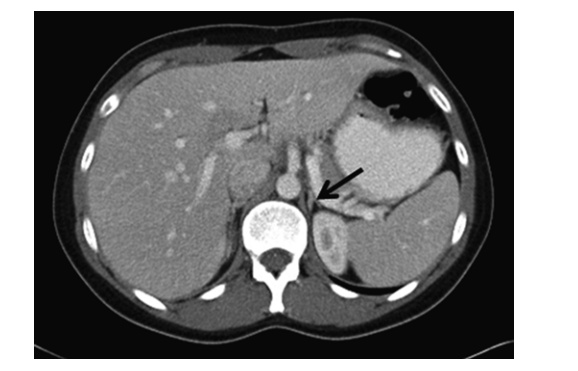

An incidentaloma is an incidentally discovered mass seen on imaging performed for an unrelated reason. Approximately 5 % of patients who undergo an abdominal CT scan will have an incidentally discovered adrenal mass. The incidence increases with patient age, with up to 10 % of patients having adrenal nodules on autopsy studies.